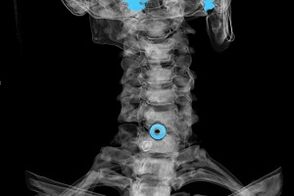

تشخیص بر اساس علائم مشخصه و همچنین با استفاده از موارد زیر انجام می شود:

- اشعه ایکس. این روش، به ویژه در آخرین مراحل توسعه پوکی استخوان، بی اثر است.

- MRI (تصویربرداری رزونانس مغناطیسی) ستون فقرات گردنی. روشی که به شما امکان می دهد ساختارهای استخوانی، فتق دیسک های بین مهره ای، اندازه و جهت رشد آنها را ببینید.

- توموگرافی کامپیوتری. راه حلی کمتر موثر نسبت به MRI، زیرا تعیین وجود و اندازه فتق دشوار است.